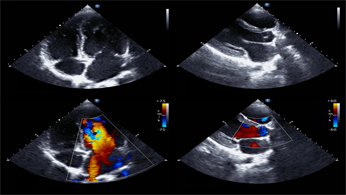

L’ecocardiogramma è una tecnica che si basa sull’impiego di ultrasuoni e consente di vedere dall’interno sia le pareti del cuore sia le sue strutture interne (come le valvole) e di valutare esattamente la contrattilità del cuore globale.